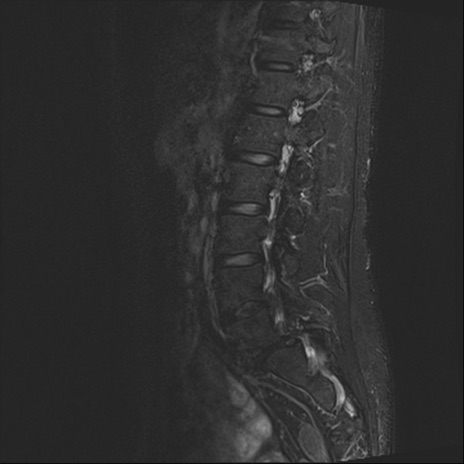

腰椎MRI

T2WI(横断像)

横断像と矢状断像